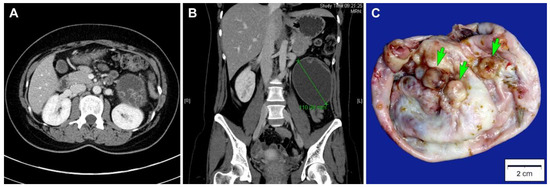

A 27-year-old Korean woman presented with abdominal pain. She had no previous gynecological history. An abdominopelvic computed tomography scan revealed a well-circumscribed, thick-walled cystic mass located between the left kidney and descending colon with a diameter of 11 cm (Figure 1A). The unilocular cystic mass in the left retroperitoneal space had a number of daughter cysts (Figure 1B). No abdominopelvic seeding or lymph node enlargement was identified. Based on the preoperative diagnosis of a primary retroperitoneal tumor, surgical mass excision was performed. The bilateral adnexa, kidneys, liver, and pancreas were unremarkable. A simple tumor excision was performed without intraoperative rupture.

Grossly, the inner surface of the unilocular cystic mass showed some nodular elevations measuring up to 1.2 cm (Figure 1C). Histologically, the tumor consisted predominantly of a thick fibrous cystic wall with multiple areas of mural hemorrhage and chronic inflammation (Figure 2A). A confluent proliferation of pseudostratified mucin-containing columnar epithelium was noted (Figure 2B). In some areas, extensively dilated glandular lumina contained an admixture of mucins, blood, and numerous inflammatory cells. The neoplastic glands varied in size and shape. The lining epithelium was partially denuded, and the subepithelial stroma was characterized by severe inflammation, foreign body reaction, and fibrosis due to mucin spillage. The mucin-containing epithelium demonstrated a spectrum of borderline and malignant morphologies. Most parts of the tumor showed histological features identical to those of ovarian mucinous borderline tumors; however, several areas showed high-grade nuclear atypia including severe enlargement, pleomorphism, prominent nucleoli, increased mitotic activity, and frequent atypical mitotic figures (Figure 2C). In addition to high-grade nuclear atypia, a loss of epithelial polarity, intraluminal papillary epithelial projections, a micropapillary growth pattern, and a cribriform architecture—features characteristic of intraepithelial carcinoma—were also present (Figure 2D,E). A few microinvasive foci, showing tumor cells that formed clusters or papillae or that were scattered individually in inflammatory stroma, were also noted (Figure 2F). We also identified some areas showing mucinous carcinomas with an expansile invasive pattern (Figure 2G), with little or no intervening stroma and extensively dilated glandular lumina containing necrotic debris (Figure 2H). Taken together, this retroperitoneal tumor was diagnosed as a mucinous carcinoma showing a histological spectrum of a mucinous tumor, including a mucinous borderline tumor associated with multifocal microscopic intraepithelial carcinoma, microinvasive mucinous carcinoma, and overt mucinous carcinoma with an expansile invasive pattern.

Figure 1. Imaging and gross findings. (A) Abdominopelvic computed tomography scan in axial view, which revealed a thick-walled cystic mass in the left retroperitoneal space. The mass had some daughter cysts. (B) Abdominopelvic computed tomography scan in coronal view, which revealed a well-circumscribed, ovoid unilocular cystic mass with a diameter of 11 cm. (C) Grossly, the inner surface of the mass showed some round-to-ovoid, variegated mural nodules (green arrows), measuring up to 1.2 cm in the greatest dimension.